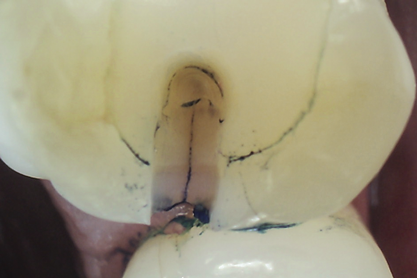

Once a significant asymptomatic enamel crack is diagnosed, to determine its extent the crack is exposed and traced using a minimally invasive exploratory fissurotomy as well as caries removal and/or existing restoration removal whenever indicated (Figure 6 and Figure 7).2,3,17 If the crack is limited to enamel and does not extend into dentin, it can be completely eliminated and treated similarly to caries whereby the condition of the remaining tooth structure dictates the type of the restoration placed and the materials used (Figure 8). For example, moderate-sized cavity preparations can support bonded direct intracoronal resin-based composite restorations (Figure 9).25 This is generally interpreted as cavity preparations in which the isthmus width is less than 50% of the intercuspal distance and the remaining enamel is sound and well supported by dentin. Occlusal adjustment, including removal of excursive interferences, might also be necessary to eliminate localized heavy occlusal forces that are predisposing the tooth to cracking.10,19,26Occlusal guards also can be fabricated to protect teeth from the damage caused by on- going bruxism.19

Fig 6. Methylene blue dye staining revealing asymptomatic enamel marginal ridge crack of a maxillary left first molar (mesio-occlusal view).

Figure 6

Fig 7. Existing restoration removal and crack fissurotomy revealing enamel crack (arrow) and caries in tthe tooth shown in Fig 6.

Figure 7